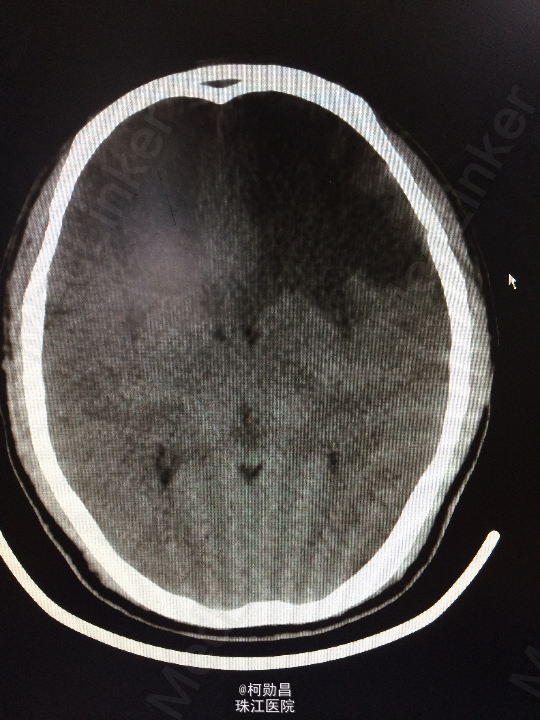

主诉:头痛伴左眼视力下降半年 病史:患者46岁男性,缘于半年前无明显诱因出现头痛,当时未予特殊处理,后症状进行性加重,并发左眼视力下降,于当地医院行头颅CT及MR检查提示颅内占位,为进一步治疗而入我院。 既往病史:5年前曾患鼻咽癌

查体:神志清楚,对答流利,左侧眼裂变小,左侧瞳孔散大,直径4mm,对光反射迟钝,左眼视力下降。右侧正常。 辅助检查:头颅MR提示前颅底筛沟通病变

诊断:鼻咽癌脑转移 处理:全麻下行颅筛沟通占位切除术,术后病理提示:鼻咽非角化鼻咽癌脑转移